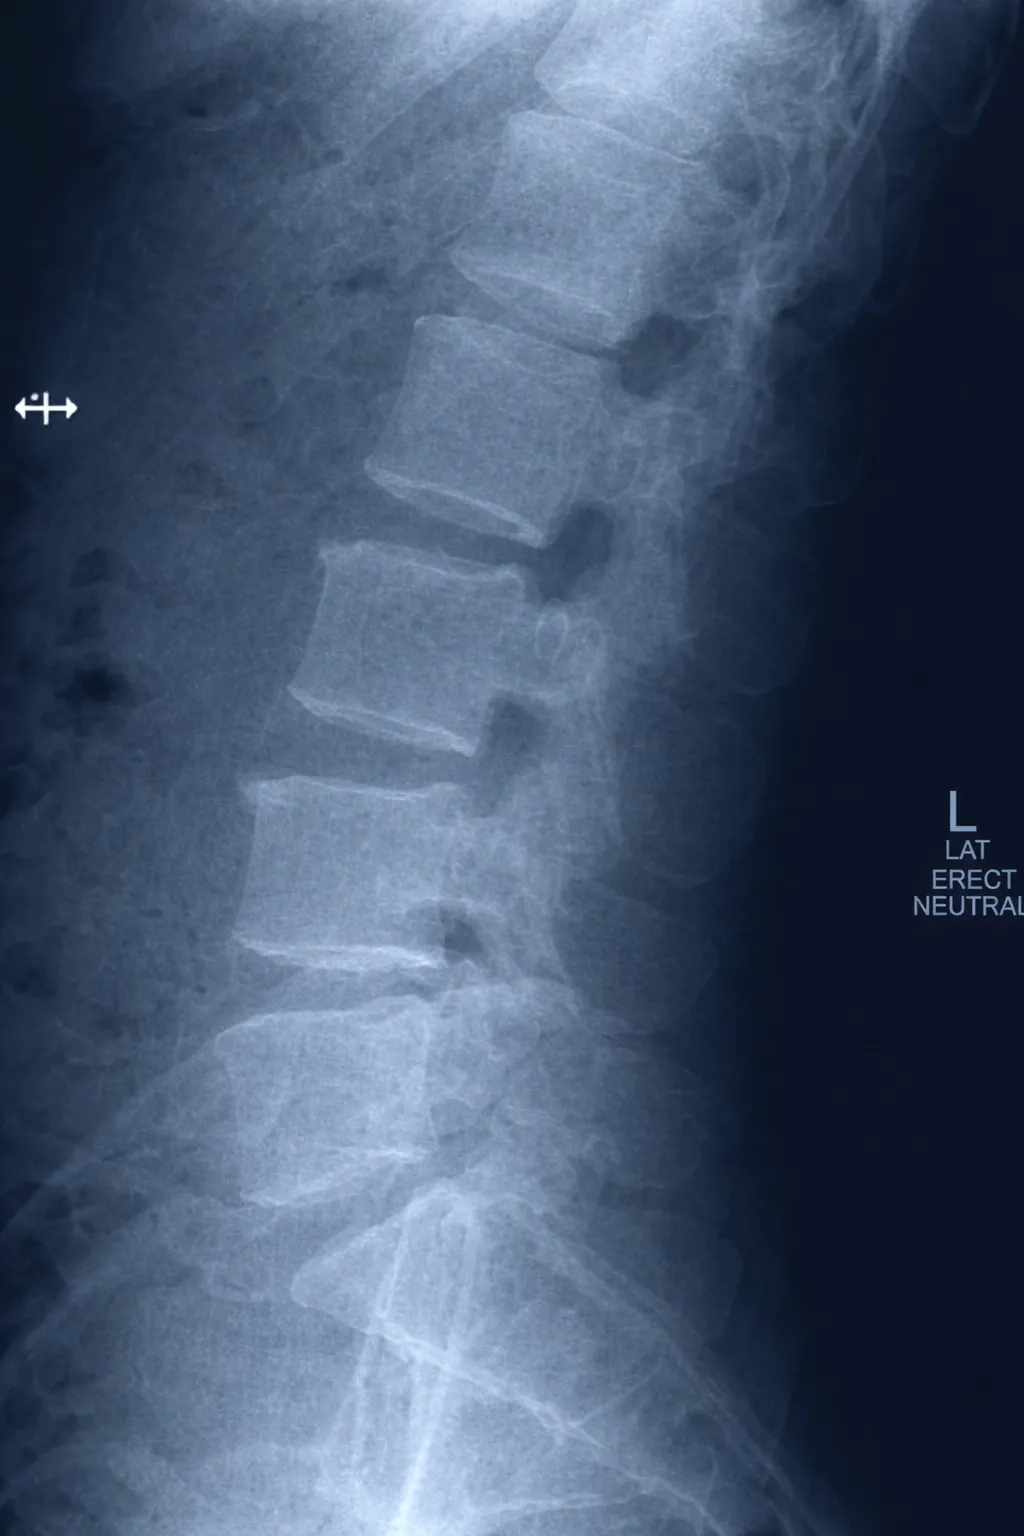

Spinal Instability & Symptomatic Disk, Joints and Ligaments

Platform identifies imaging findings related to spinal instability, symptomatic disc abnormalities, facet joint changes, and ligamentous injuries for physician review and clinical correlation.

Multi-Level Spine Analysis Example

Imaging shows findings consistent with instability at L4/5 and L5/S1 following prior percutaneous disc procedure. Board-certified physician review recommended for treatment planning.